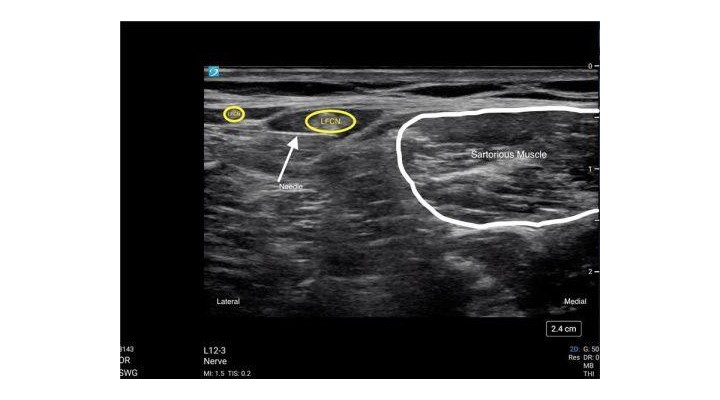

- Identify the Lateral Femoral Cutaneous Nerve just lateral to the Sartorious Muscle. The LFCN is a hyperechoic structure located at an approximate depth of .5-.75cm.

- Use the in-plane needle technique with a lateral to medial approach to target the Lateral Femoral Cutaneous Nerve.

- Scan lateral to identify the Sartorious Muscle. Follow the Sartorious Muscle to its lateral border.